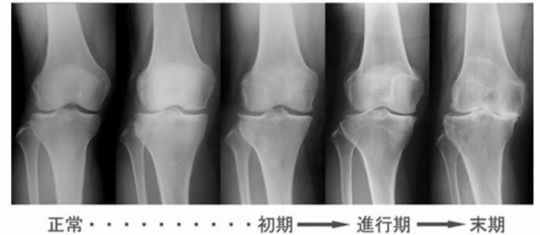

変形の進行度合い

膝が内側に入ると膝の中ではどのような事が起きているのかが想像できます。

膝の中に剪断力と圧縮力が生まれ、関節の中にある半月板を傷つけてしまいます。

また、膝の内側と外側にかかる圧ストレスにも変化が出てきます。

膝が内側に入るとせんだん力で関節の中を痛めやすい

通常膝がまっすぐに落ちた時の膝の圧ストレスは内側50% 外側50%になります。

しかし、膝が内側に入ったら内側へのストレスは50%から70%や80%に変わり、外側へのストレスは50%から20%や30%へと圧ストレスが変化する。

この膝の中に加わる剪断力と圧縮力を改善させないと膝の変形は時間と共に進行していきます。